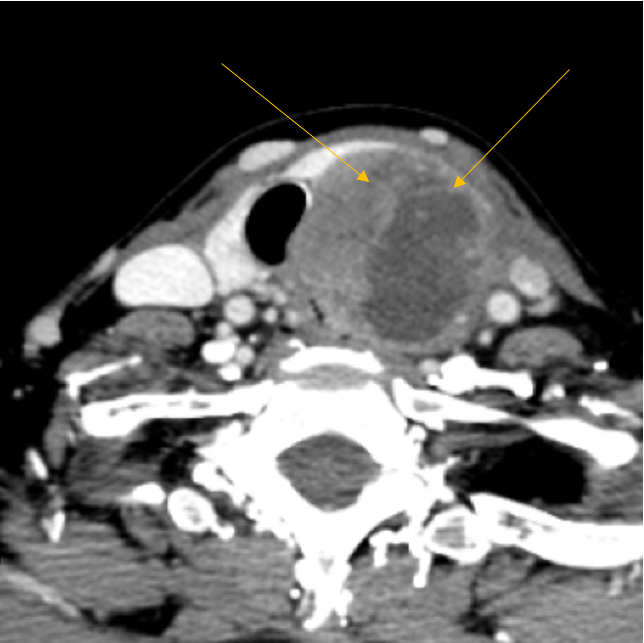

5 Best Ways to Diagnose Thyroid Cancer

From www.thyroidcancer.com

5 Best Ways to Diagnose Thyroid Cancer Light Thyroid Cancer Research has already identified some factors that affect the likelihood of developing tc. Compared with the lowest quintile of light exposure at night, the highest quintile was associated with a 55 percent higher risk of developing the disease. Most thyroid cancers aren't likely to recur, including the most common types of thyroid cancer — papillary thyroid cancer and follicular. Model. Light Thyroid Cancer.